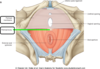

The perineum is the region of the trunk below the pelvic diaphragm and bounded by the pelvic outlet. It is subdivided by a line connecting the ischial tuberosities into 2 triangles that do not communicate. They are:

–anterior urogenital triangle(horizontal)

–posterior anal triangle (almost vertical)

The urogenital triangle consists of what 5 things?

- Skin

- Superficial fascia

- Superficial perineal pouch

- Perineal membrane

- Deep perineal pouch

The Superficial fascia of the urogenital triangle consists of 2 layers, a fatty layer and a membranous layer known as……………….

Colle’s fascia

The superficial perenial pouch is located between the colles’s fascia and the perineal membrane. It does what?

anchors external genitalia

The deep perineal pouch is located between the pelvic diaphragm and the perineal membrane. It includes what important structure?

external urethral sphincter